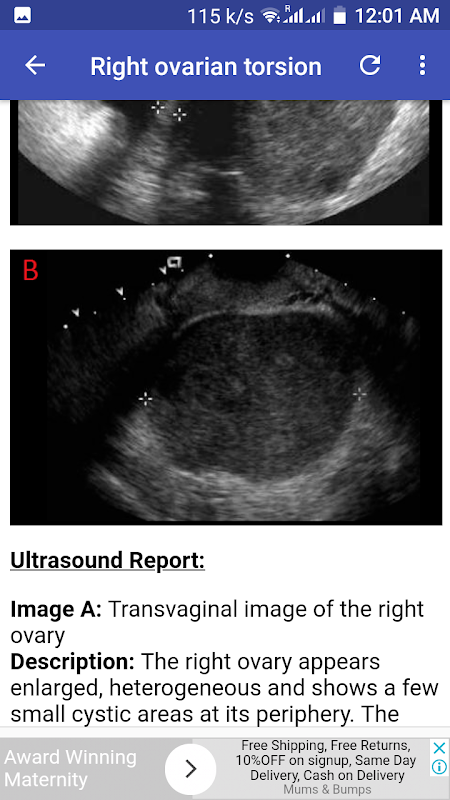

Right ovarian torsion